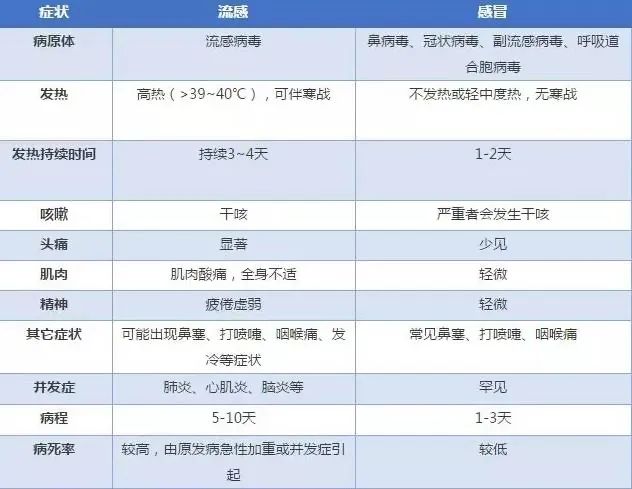

从网友们的描述来看,甲流患者多出现了咳嗽、咽喉痛、高热等症状,同时伴有头痛、肌肉酸疼等全身不适。但看这些症状,与新冠症状并无不同之处。那么,又该如何判断自己是得了甲流还是新冠呢?